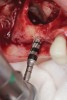

A lateral sinus window was created using a combination of a round fissure bur and piezosurgery device tip (Figure 3). The elevation of the Schneiderian membrane was also performed with a piezosurgery device along with hand instruments (Figure 4). A type 1 bovine cross-linked collagen membrane (Mem-Lok®, BioHorizons, biohorizons.com) soaked in liquid platelet-rich fibrin (PRF) was placed over the Schneiderian membrane along with two PRF membranes prior to the use of OD burs (Figure 5). The OD burs were then utilized to densify bone on the osteotomy walls (Figure 6). The bone graft, composed of a 50/50 mixture of cortico-cancellous allograft and xenograft mixed with PRF fragments, was used to fill the bone defect in the sinus, followed by implant placement (Figure 7). Primary implant stability was measured at 60 Ncm. Lastly, a collagen membrane was placed over the lateral window with fixation and covered by two PRF membranes to enhance soft-tissue healing (Figure 8). Primary closure was obtained using 3.0 polytetrafluoroethylene (PTFE) sutures (Figure 9).

Fig 3. Lateral sinus augmentation; an initial window was created using a combination of a round fissure bur and, as shown, a piezosurgery device tip.

Figure 3